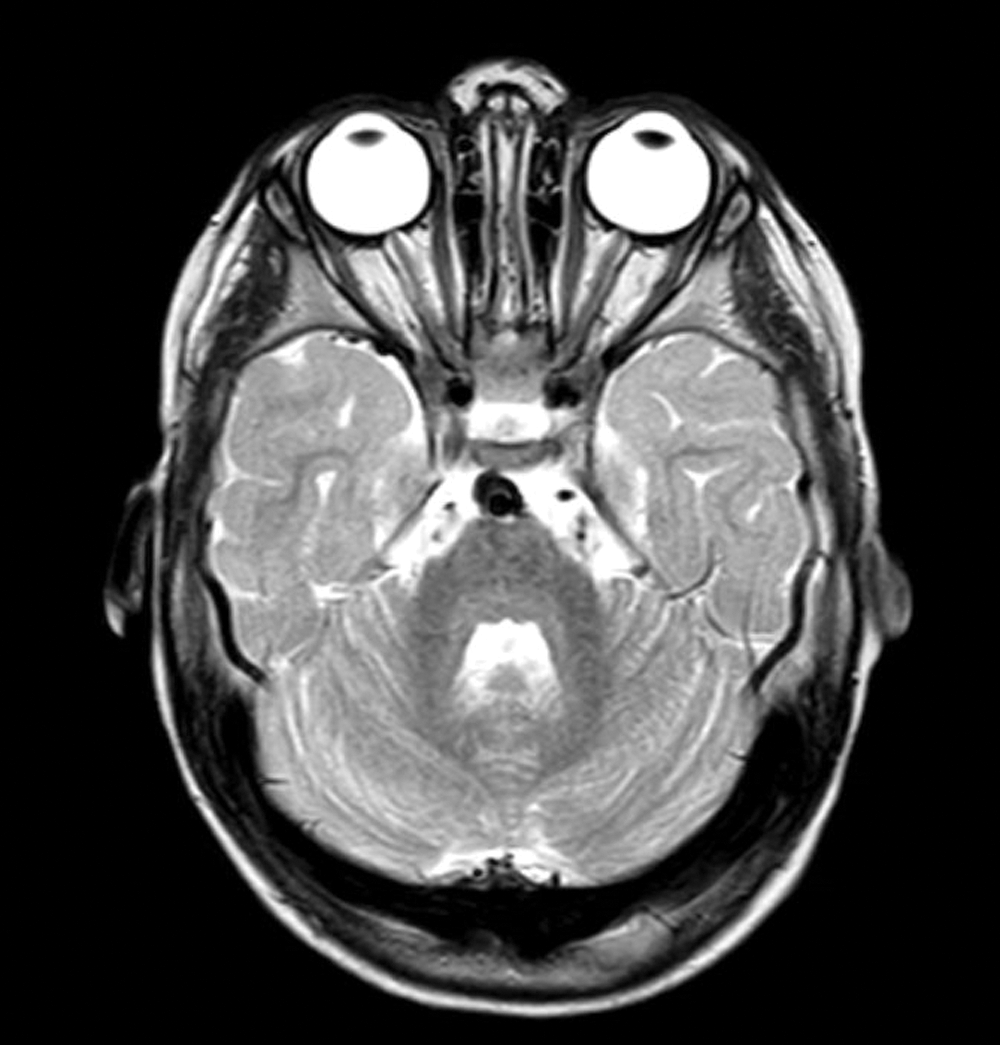

Her cardiac testing demonstrated unchanged findings on her echocardiogram, with normal morphologic left ventricular function, trivial right atrio-ventricular valve insufficiency without stenosis, trivial aortic insufficiency, and low-velocity laminar flow through the superior cavo-pulmonary anastomosis. The atrial septum was unrestrictive. She was admitted for an elective cardiac catheterization one week later to exclude elevated Glenn pressure as a possible cause of intermittent headache as the cause of the irritability and behavioral changes since no other obvious etiology was present at the time. Her overall hemodynamics were unremarkable, with the Glenn pressure 14 mmHg, trans-pulmonary gradient 4–5 mmHg, well preserved cardiac index of 5.5 l/min/m2, pulmonary-systemic shunt ratio of 0.63:1, and pulmonary vascular resistance of 1.4 Wood Units × m2. There was no stenosis within her Glenn anastomosis or branch pulmonary arteries. She did have modest aorto-pulmonary collateral vessels originating from her bilateral internal mammary arteries, and they were occluded with micro-embolization particles. There were no veno-venous collateral vessels. Her post catheterization recovery was unremarkable, but she was again admitted one week after discharge with unremitting, and possible deteriorating symptoms of irritability, gait instability and poor appetite. Further initial clinical work-up, which included renal and liver function testing, abdominal ultrasound, and celiac, thyroid, lead, infectious and rheumatologic screening bloodwork were all negative. A neurology consultation was obtained, prompting brain magnetic resonance imaging which was positive for mild diffuse cerebral volume loss; upon later review, there was bilateral posterior flattening of the globes evident (Fig. 1). With no obvious etiology, the patient was treated for possible migraine headache, which resulted in marked but transient symptomatic improvement, with a return of symptoms hours later. At that point, an Ophthalmology examination was obtained, demonstrating bilateral papilledema. This was followed shortly thereafter with a diagnostic lumbar puncture, notable for elevated opening pressure of 28 mmHg. All cerebrospinal fluid studies were negative. Symptoms were greatly improved after the lumbar puncture.

Figure 1: Axial T2 MRI of the brain demonstrating posterior globe flattening. There is normal brain parenchyma, vessels and cerebrospinal fluid flow through the craniocervical junction